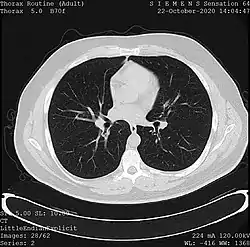

Medical imaging

One frame of a CT scan of the chest showing the heart and lungs.